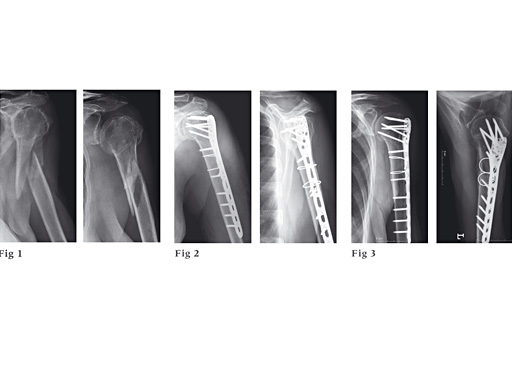

87-year-old woman fell down the stairs, fracture type 12-C1.

Fig 1

Preoperative x-ray.

Fig 2

Postoperative x-ray.

Fig 3

Follow-up after 6 months.

With kind permission of Michael Plecko, MD.